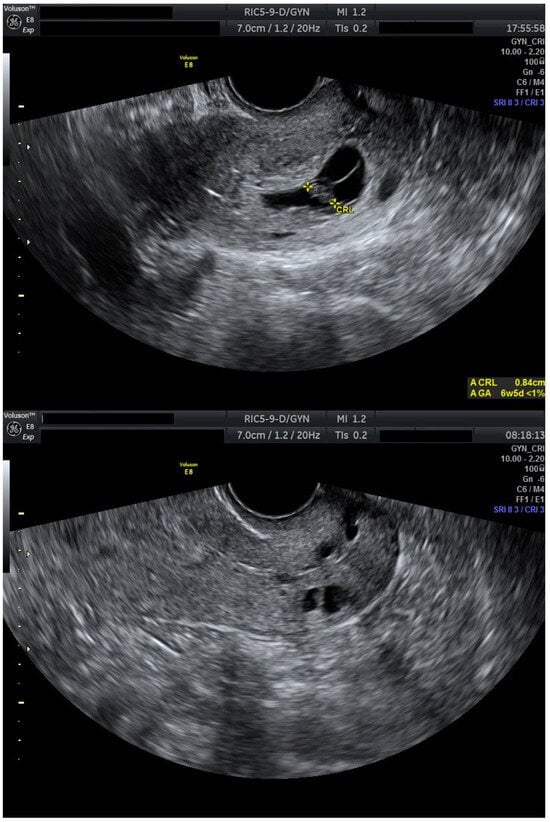

After 72 h, the patient was re-evaluated. Cervical stromal vascularity presented no remaining gross vascularity. Subsequently, starting at the time of this ultrasound evaluation, the patient received misoprostol 0.2 mg intravaginally, every 6 h. This induced partial expulsion of the intrauterine pregnancy into the cervical canal, where it became impacted adjacent to the cervical gestational sac. Despite continued uterotonic administration, the cervical gestation did not expulse. Thus, a suction curettage was performed. The procedure was uneventful, with minimal blood loss, and post-procedure ultrasound confirmed complete evacuation of both gestations and restoration of a normal endometrial cavity and cervical canal (Figure 3).

Figure 3.

Cervical canal before and after suction curettage (Day 13). Transvaginal ultrasound evaluation: sagittal view through the cervical canal. A total of 24 h after initiation of misoprostol expulsion therapy. Impacted gestational sacs in the cervical canal before curettage and the empty cervical canal immediately after suction curettage. Patient information is anonymized.